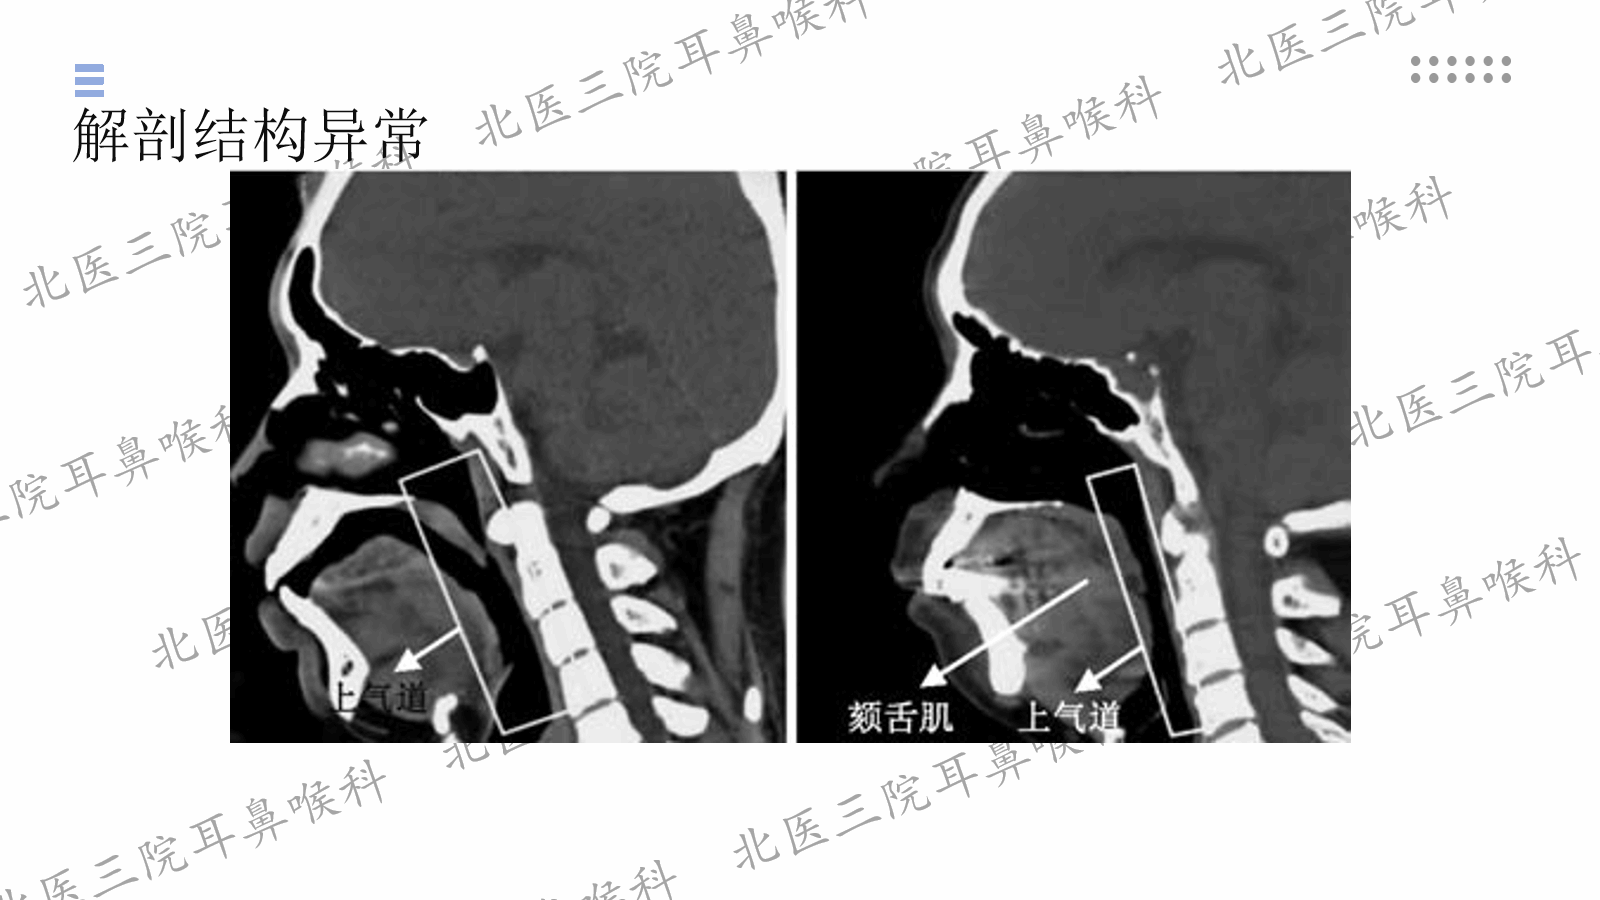

2025.7研究生读书报告:阻塞性睡眠呼吸暂停上气道塌陷机制与研究进展